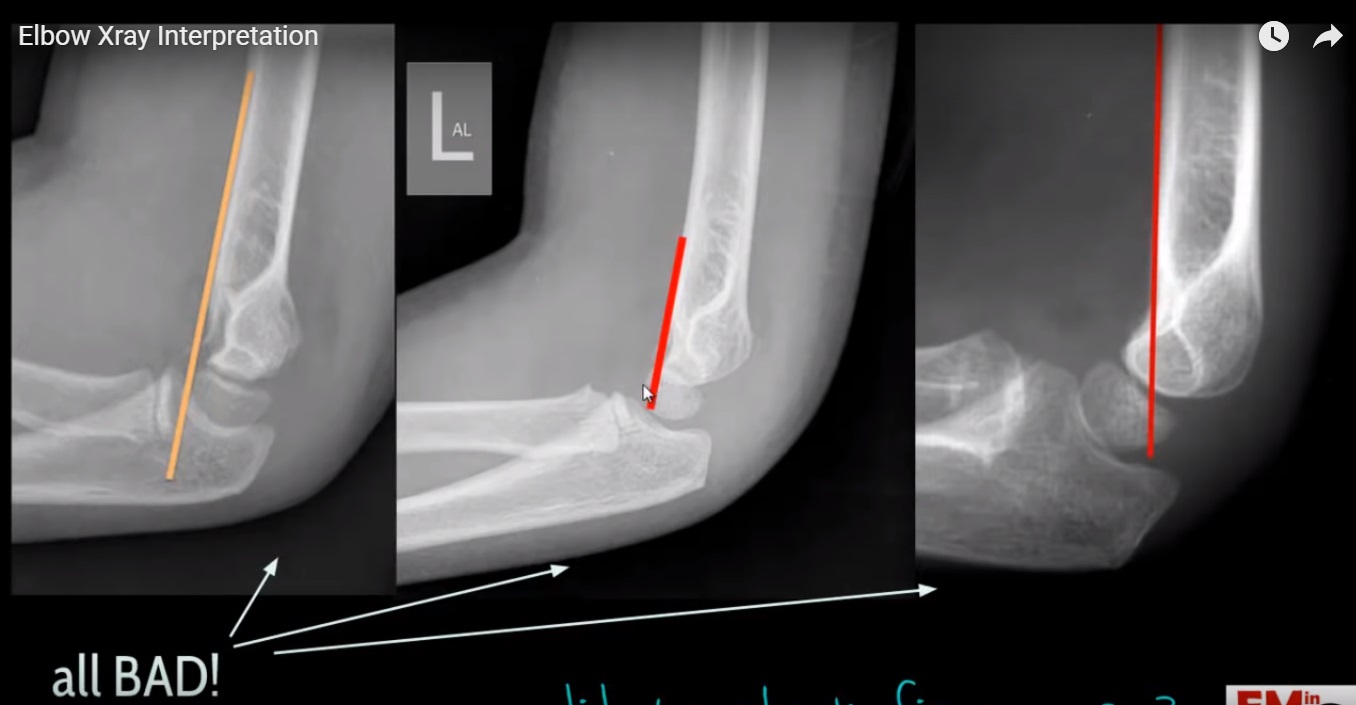

What Does A Elbow X-Ray Show . Reading elbow radiographs (xrays) is a key skill used by physicians to help diagnose the cause of the patients elbow pain. An x ray image of the elbow joint provides information for assessment, evaluation and diagnosis of elbow joint disease process or injury, such as fracture and gives. The elbow series is a set of radiographs taken to investigate elbow joint pathology, often in the context of trauma. A recommended systematic checklist for. Demonstrate widening or narrowing depending on the clinical condition. Ulnohumeral and radiocapitellar joint spaces are well seen and can. The order in which you interpret the radiograph is personal preference.